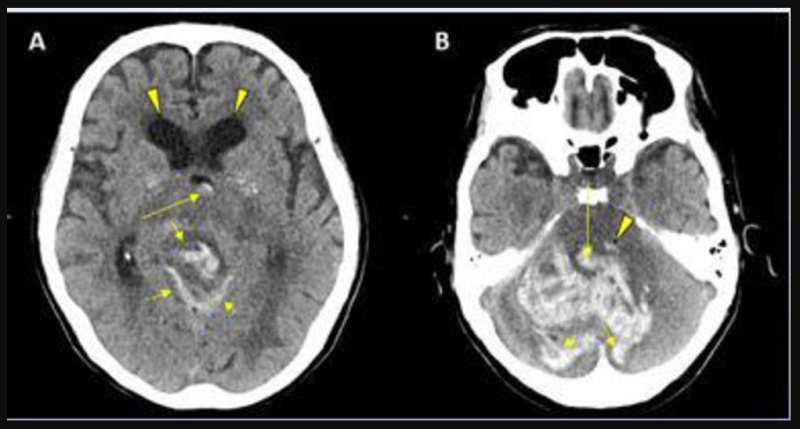

This photo gallery shows the variety of radiological presentations of COVID-19 (SARS-CoV-2) in medical imaging, including computed tomography (CT), radiograph X-rays, ultrasound, echocardiograms and magnetic resonance imaging (MRI). The radiology images show examples of typical COVID pneumonia in the lungs and the numerous complications the virus causes in the body in multiple organs, including the brain, kidneys, heart, abdomen and vascular system.

Ultrasound, especially hand-held ultrasound imaging devices, have become a primary imaging modality for novel coronavirus because of the ease to bag the device and sterilize it after use. CT and mobile X-ray systems are also used as front-line imaging systems for COVID-positive or suspected COVID patients.